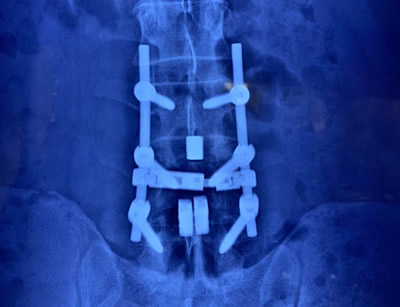

IMÁGENES

Galería de imágenes